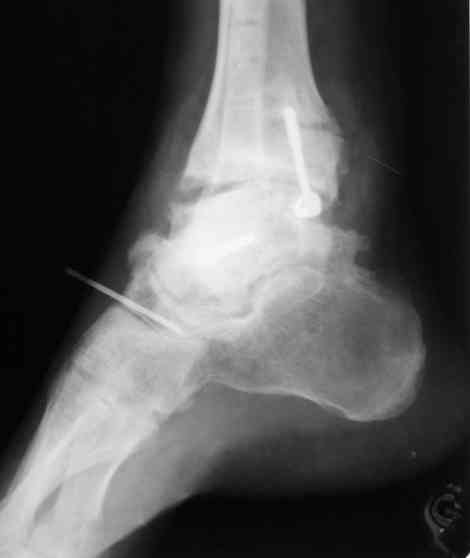

Решили не связываться с остеосинтезом, а сделать сразу берцово-пяточный блок. Снимки в приложении.

По завершении удлинения, наверно, заштифтуем.

Комментарии/критика приветствуются.